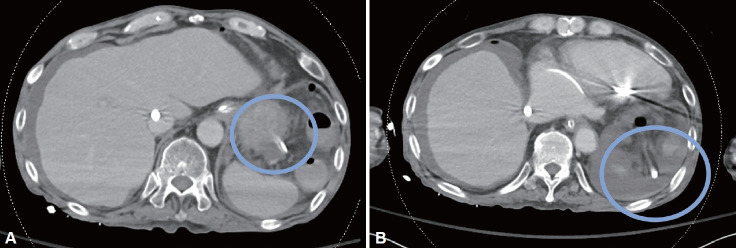

鼻胃管插入是一种常见的常规手术,用于各种目的。胃管引起的胃穿孔很少见,但可能危及生命。我们报告一个罕见的病例涉及延迟胃穿孔引起的胃管在成人终末期心力衰竭。

Nasogastric (NG) tube insertion is a common and routine procedure that is performed for various purposes. Gastric perforations caused by NG tubes are rare but potentially life-threatening. We report a rare case involving a delayed gastric perforation caused by an NG tube in an adult with end-stage heart failure.